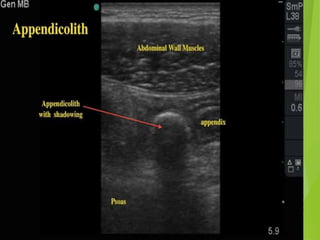

ACUTE APPENDICITIS

Findings on plain film

 Normal

 Focal ileus

 Appendicolith

 Mass

 Free air is very rare

Longitudinal and transverse sonogram show an enlarged

appendix (arrows) surrounded by hyper echoic inflamed fat

(arrowheads).